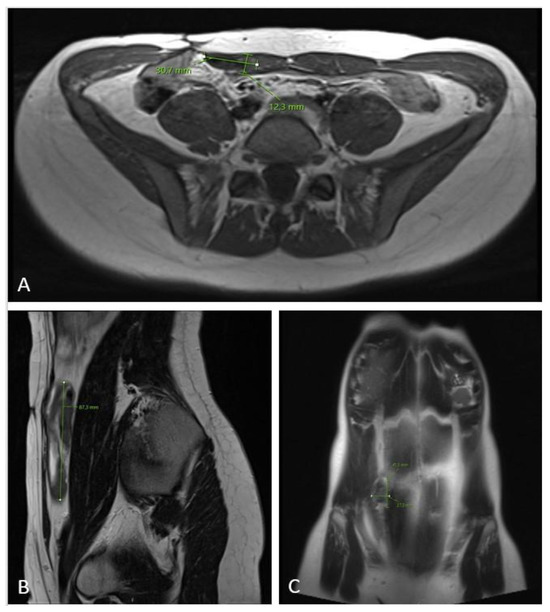

Figure 6.

MRI scan ((A)—axial plane; (B)—sagittal plane; (C)—coronal plane) 12 months after chemotherapy showing significant tumor regress, sized only 1.2 × 3.7 × 8.7 cm.

The 3-month MRI control showed a stable tumor size; however, the MRI check at the 6-month follow-up showed significant tumor growth progression (Figure 4), sized 10.5 × 6.2 × 17.5 cm in craniocaudal diameter located in the musculus rectus abdominis on the right side. She was recommended to stop oral contraceptives and preventive devices (IUD) containing estrogen and/or progesterone and was referred to the National Oncology Center for further treatment, where the tumor board determined to administer chemotherapy, and the treatment started with three cycles of Caelyx (doxorubicin hydrochloride), 40 mg/m2 every fourth week, with MRI control afterwards. The patient suffered side effects in form of skin rashes, allergic respiratory problems, and mucositis. She received 60 mg of Caelyx by IV each cycle. The control MRI scan showed no effect of treatment; furthermore, there was a slight progression in the craniocaudal tumor size (12.0 × 6.6 × 20.0 cm), (Figure 5). As the oncologist awaited the latest response to chemotherapy, the further plan was to continue the same treatment options (Caelyx, although at a reduced dose, set to 30 mg/m2) due to the previous side effects. The patient underwent three further cycles with total dose of 47 mg doxorubicin at each cycle. The MRI scan after six cycles showed partial regression of the tumor, now sized 11.2 × 5.4 × 19.1 cm. She was continuously monitored by the surgeon and radiologist with MR scans every 4 months, and the 12-month scan after chemotherapy showed significant tumor regress, sized only 1.2 × 3.7 × 8.7 cm (Figure 6). Five weeks later, the patient became pregnant and was referred from the midwife for gynecological control, starting on week 12 + 4.